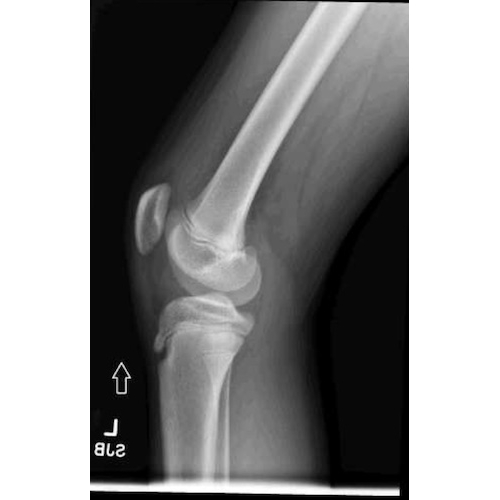

| A Knee Full Of Surprises - Page #3 | |||